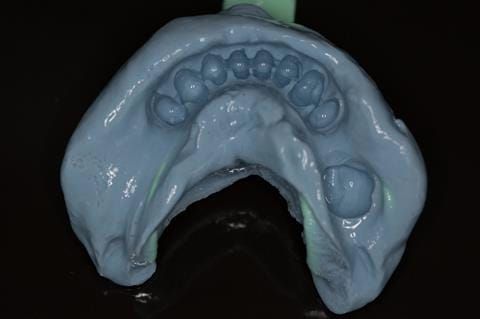

Following consultation and second discussion appointment the patient chose to have option 2 namely, a window denture - maxillary cobalt chromium based partial denture. The clinical situation and treatment process is shown in detail below with photographs. The patient was successfully rehabilitated with this and her quality of life considerably improved. The clinical work was provided by Finlay and the technical work by Rowan.